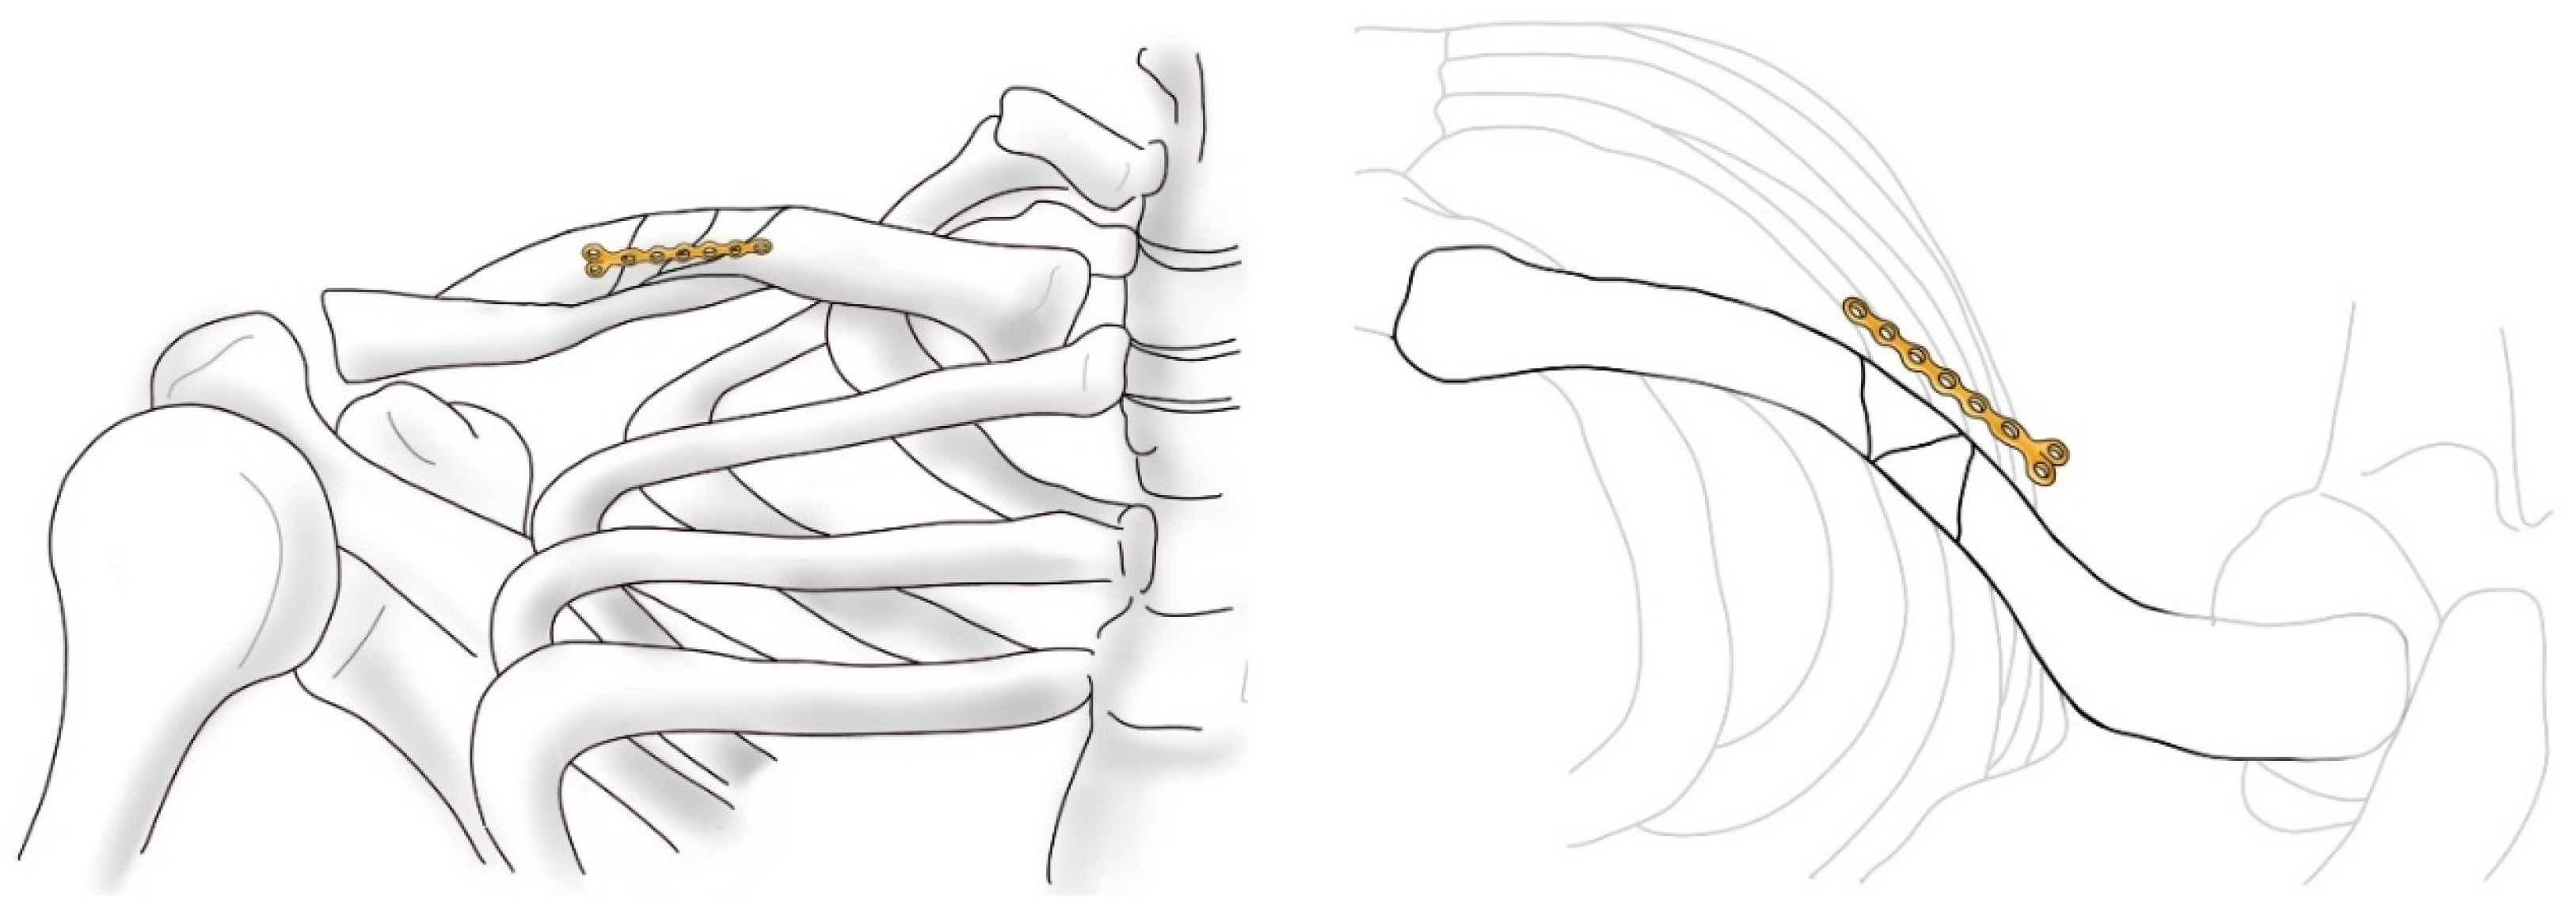

Intuitive and Minimally Invasive Surgical Technique for Comminuted Mid-Shaft Clavicle Fractures: Fixation with an Anterior Mini Plate and Superior Locking Compression Plate

2.2. Surgical Protocol